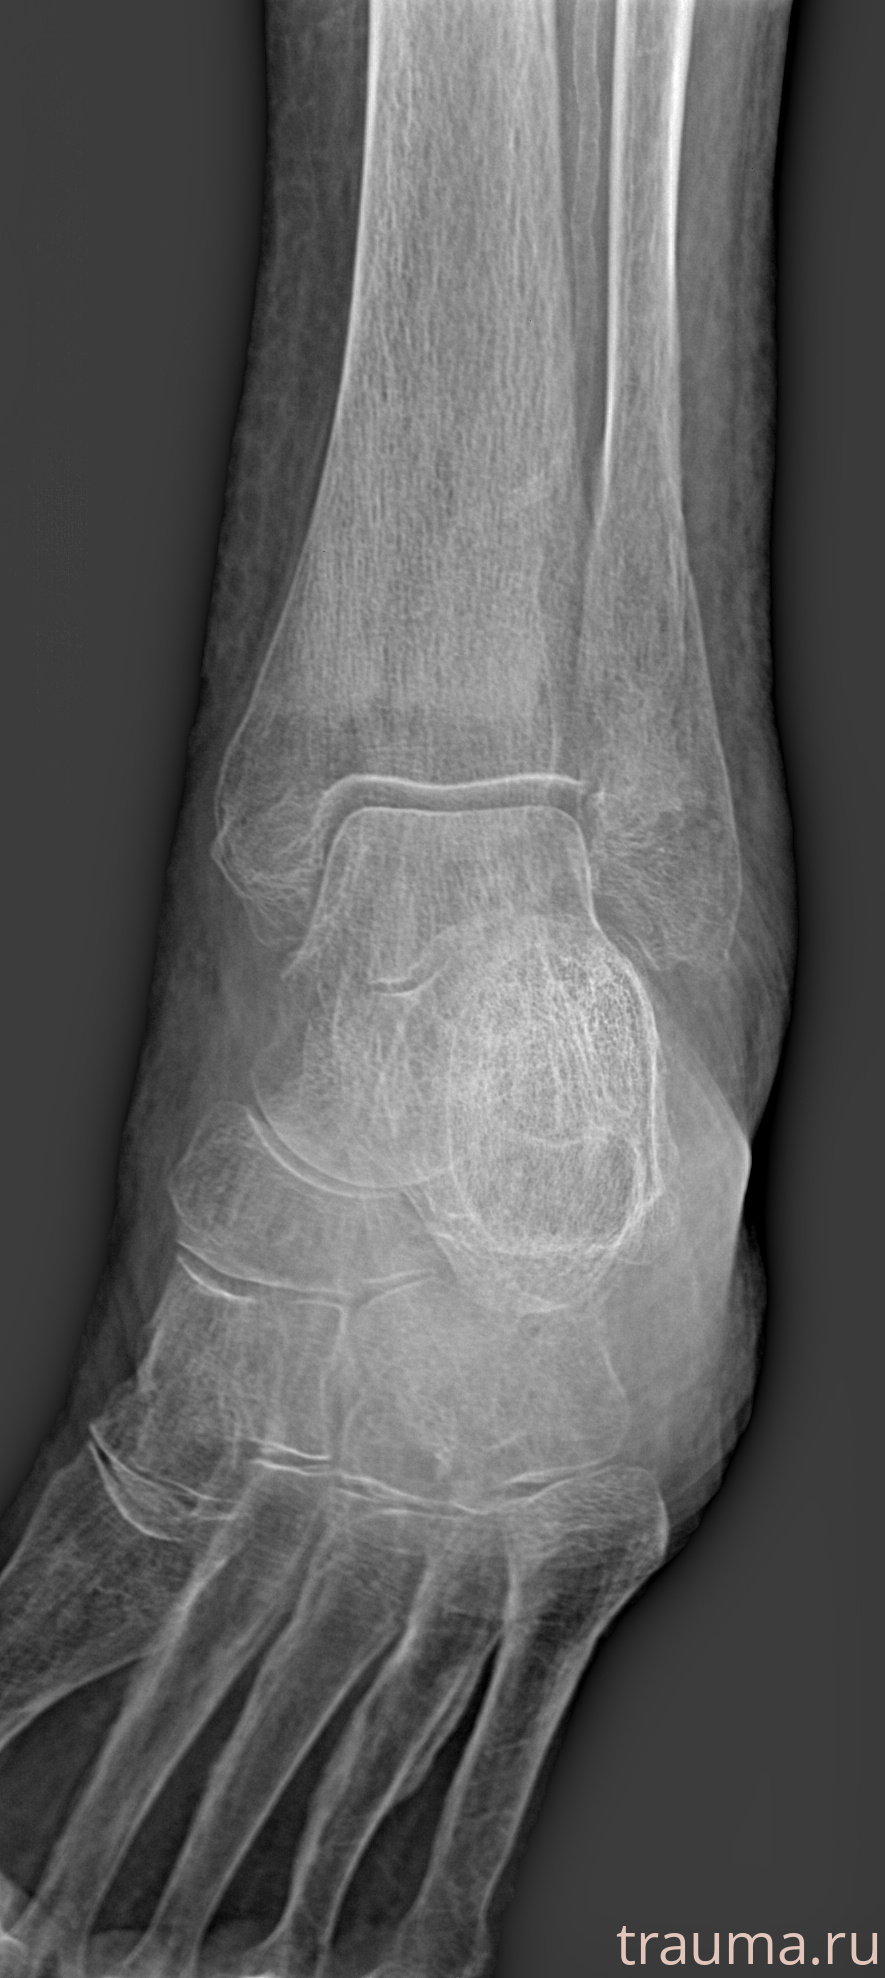

Рентгенограммы